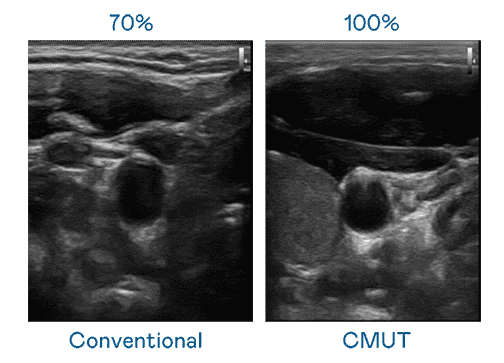

CMUT 技术是一种用电容式微机电元件来产生超音波讯号的技术。。。与传统 PZT 压电式技术相比,,,,CMUT 频宽增加 30%,,更宽频的超音波讯号让影像解析度大幅提升,,,是实现高影像品质医疗超音波扫描、、、促进精准医疗发展的关键技术。。。。

超音波影像的解析度高低,,,,首先取决于探头能发出的讯号频宽。。。尊龙z6 CMUT 可提供高清晰的超音波讯号,,提供高频宽、、高灵敏度、、、、影像纹理细节更高的超音波影像,,,,协助医护人员缩短影像判读时间及利用精准的医疗影像进行诊断。。